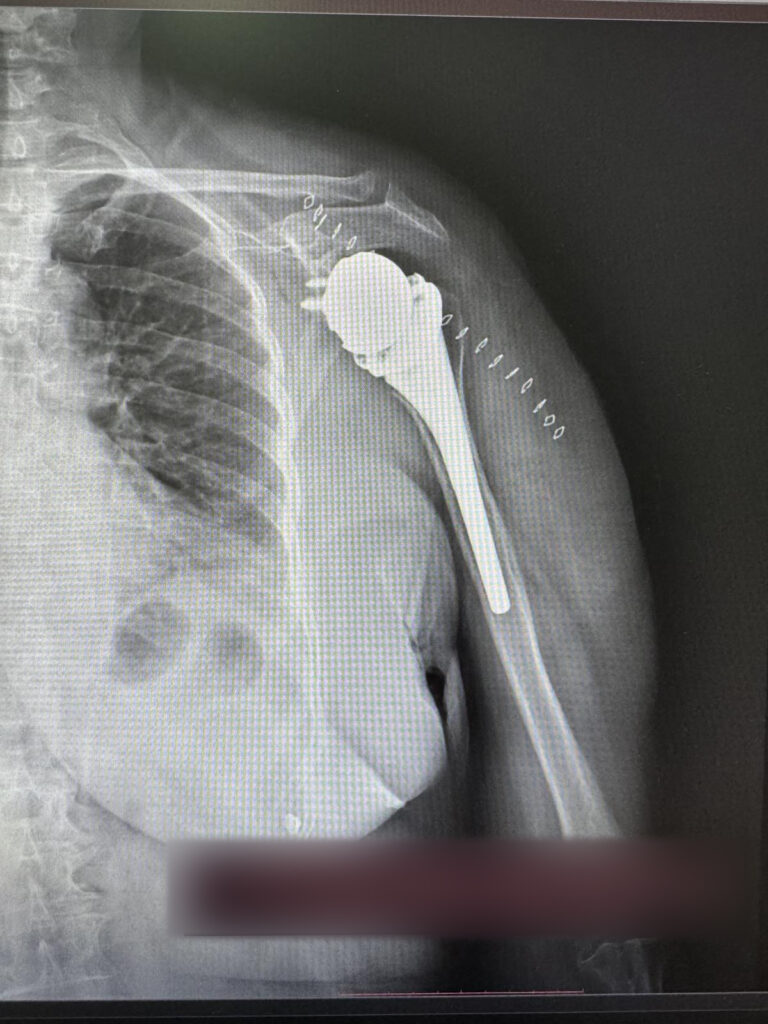

Për herë të parë në QKUK kryhen dy operacione për vendosjen e protezave të supit

Për herë të parë në Klinikën e Ortopedisë të Qendrës Klinike dhe Universitare të Kosovës janë kryer dy operacione për vendosjen e protezave të supit.

ShSKUK ka njoftuar se ekipi mjekësor në përbërje të dy ortopedëve, si dhe ekipit nga Klinika e Anesteziologjisë dhe stafit infermieror, me sukses të plotë kanë kryer këto dy operacione ortopedike.

“QKUK kishte përfituar si donacion tavolinën operative për ndërhyrje në krahë, nga Klinika me renome botërore Schulthess Klinik, Zvicër”.